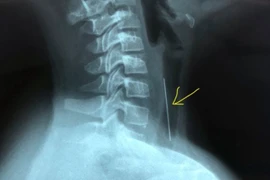

Các bác sĩ Khoa Tai Mũi Họng, Bệnh viện Việt Nam - Thụy Điển Uông Bí vừa tiến hành xử trí gắp thành công đoạn dây thép trong họng của một bệnh nhân 77 tuổi, ở Quảng Yên, Quảng Ninh.